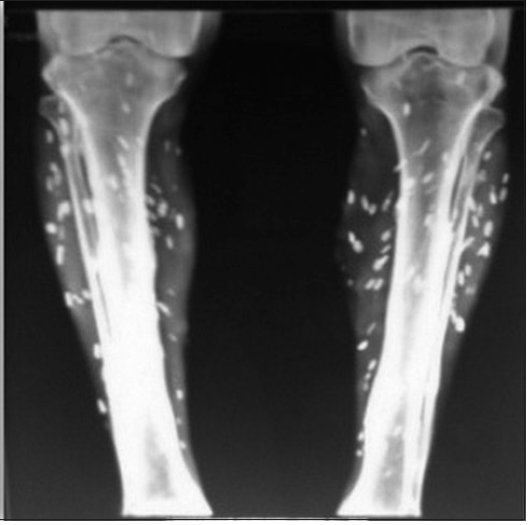

🩺 Paciente ingresa al hospital quejándose de dolor e dolor en los dedos y las muñecas. Después de un examen físico, análisis de sangr3 y una radiografía de tórax, el médico solicita inmediatamente una radiografía de cuerpo completo. Radiografía:

🩺 Paciente ingresa al hospital quejándose de dolor e dolor en los dedos y las muñecas.

Después de un examen físico, análisis de sangr3 y una radiografía de tórax, el médico solicita inmediatamente una radiografía de cuerpo completo.

Radiografía: